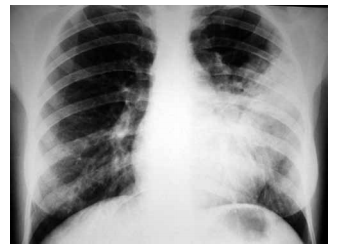

Homem, 46 anos, com antecedente de infarto agudo do miocárdio, é portador de miocardiopatia isquêmica e insuficiência cardíaca. Atualmente recebe tratamento otimizado para insuficiência cardíaca, no entanto permanece em classe funcional III (NYHA). O ecocardiograma mostra diâmetro diastólico do ventrículo esquerdo = 72 mm e fração de ejeção do VE = 34%. Holter de 24 horas: extrassístoles ventriculares frequentes, quatro episódios de taquicardia ventricular não sustentada e um episódio de taquicardia ventricular sustentada com 1 minuto de duração. O eletrocardiograma está ilustrado a seguir.

Assinale a alternativa correta em relação à redução de morbimortalidade do paciente em questão.